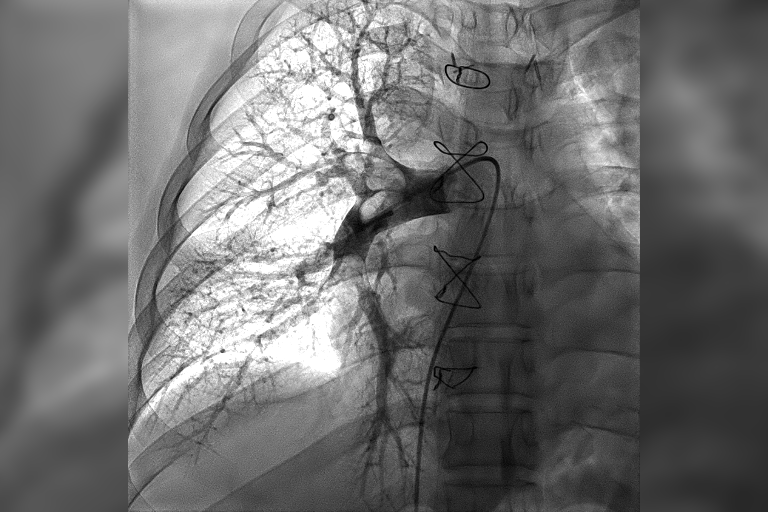

术前肺动脉造影术提示右肺动脉大面积血栓

时间就是生命。在上海市胸科医院快速急诊手术准备后,心内科副主任医师王承带着团队进入导管室。只见医生操作娴熟,选用肺动脉取栓支架系统Tendvia™,灵活地经导管,一条一条地取出大量暗红色血栓。患者即刻感觉呼吸通畅,氧饱和度上升至95%以上。术后复查肺动脉造影术提示他的右肺动脉血栓影已完全消失,肺动脉血流通畅,各项血流动力学指标也明显改善。整台介入手术用时仅用30分钟,就立竿见影地让患者转危为安。

术后复查肺动脉造影术提示肺动脉血流通畅